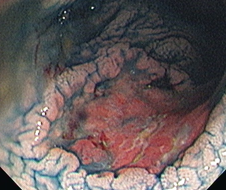

- People with ulcerative colitis and Crohn's colitis have a 2-3x increased colorectal cancer (CRC) risk (on average) compared to the general population

- Surveillance for CRC in IBD is fraught with challenges - there is a much higher Post Colonoscopy Colorectal Cancer (PCCRC) rate in IBD compared to the general population as there is an increased difficulty in detecting and resecting these lesions, as well as an accelerated cancer biology